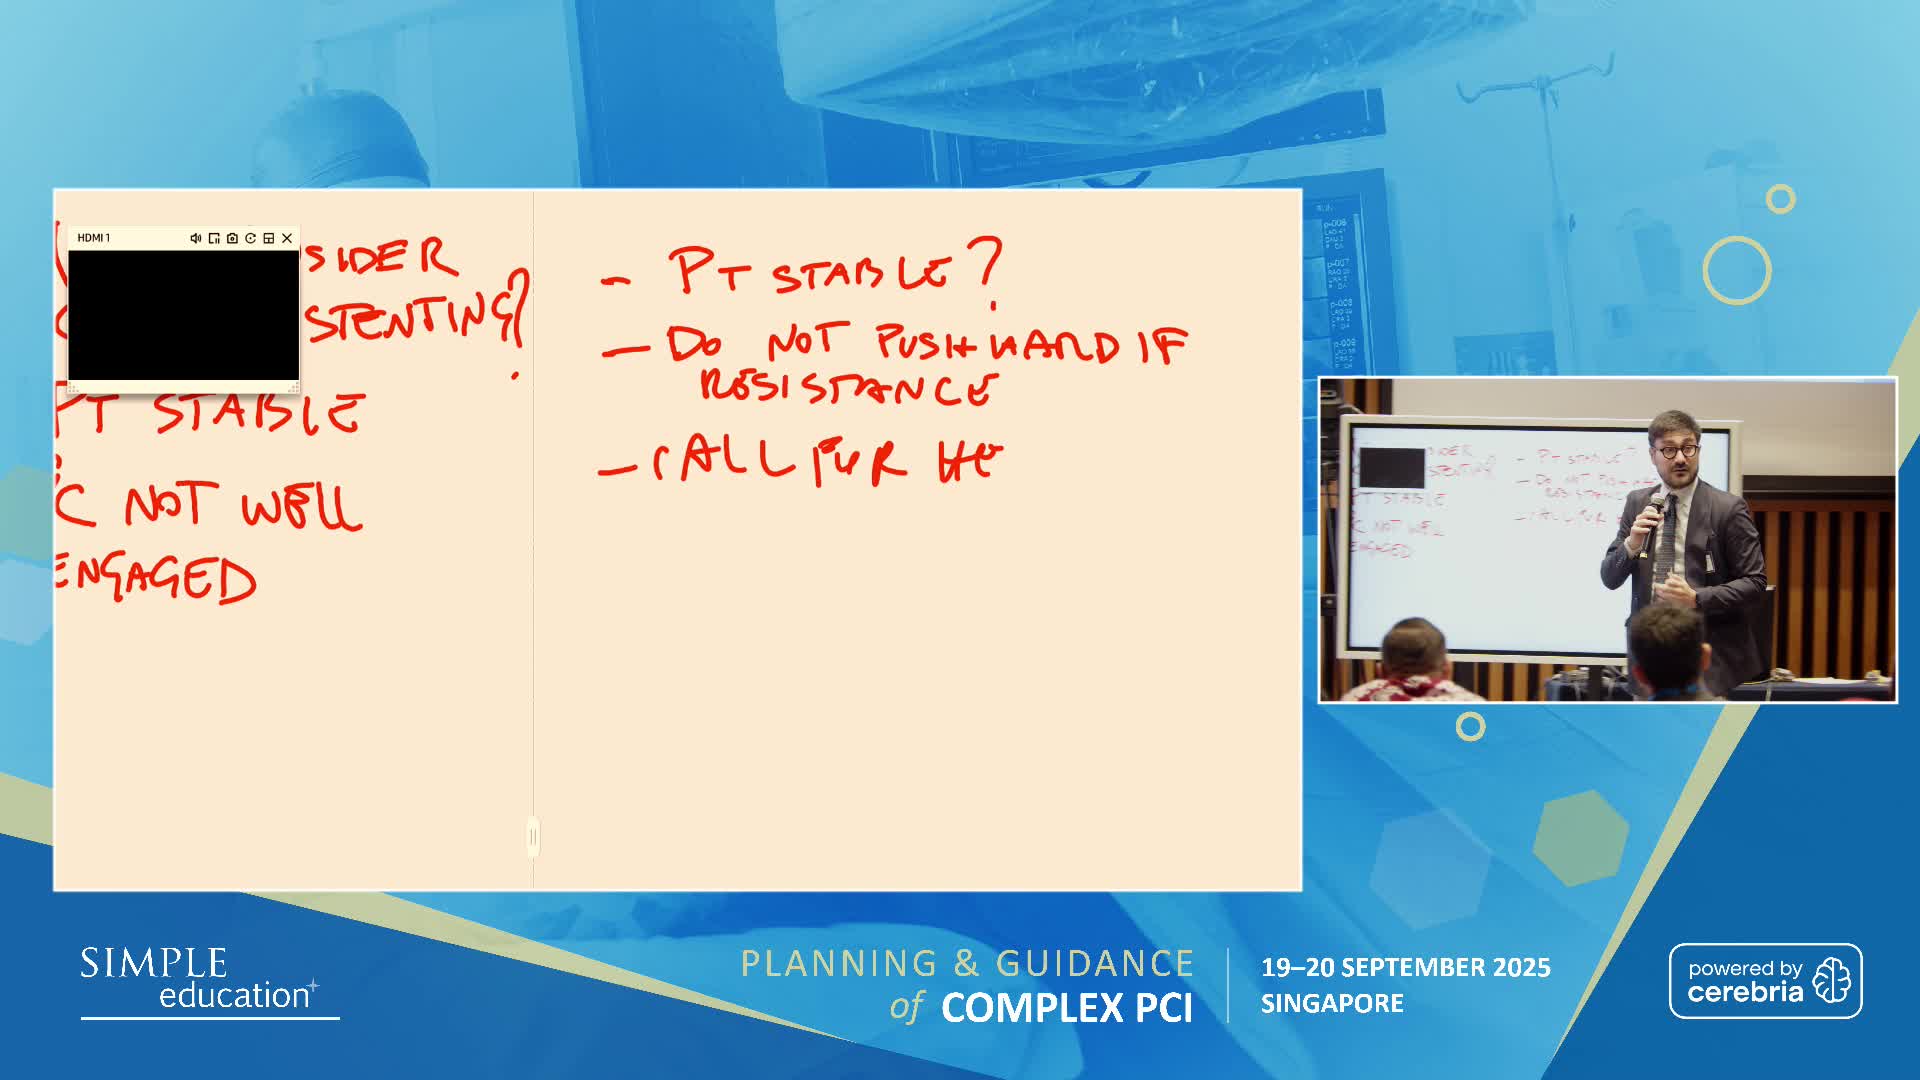

Planning and guidance of complex percutaneous coronary interventions - June 2023 Day One

Planning and guidance of complex percutaneous coronary interventions - June 2023 Day Two

Planning and guidance of complex percutaneous coronary interventions - October 2022 Day One

Planning and guidance of complex percutaneous coronary interventions - October 2022 Day 2

Planning and Guidance of Complex Percutaneous Coronary Interventions - May 2022 Day One

Planning and Guidance of Complex Percutaneous Coronary Interventions - May 2022 Day Two

Planning and Guidance of Complex PCI 23rd November 2021

Planning and Guidance of Complex PCI 22nd November 2021

Planning and Guidance of Complex PCI 12th April 2021

Planning and Guidance of Complex PCI 13th April 2021